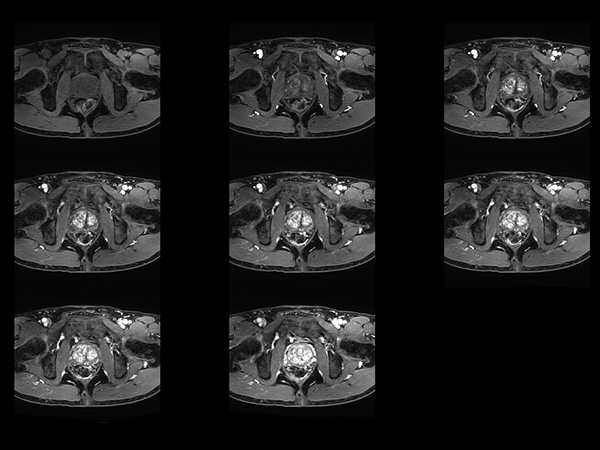

Fast Prostate imaging with SmartSpeed Precise

Kumamoto Chuo Hospital Japan

Used Solution